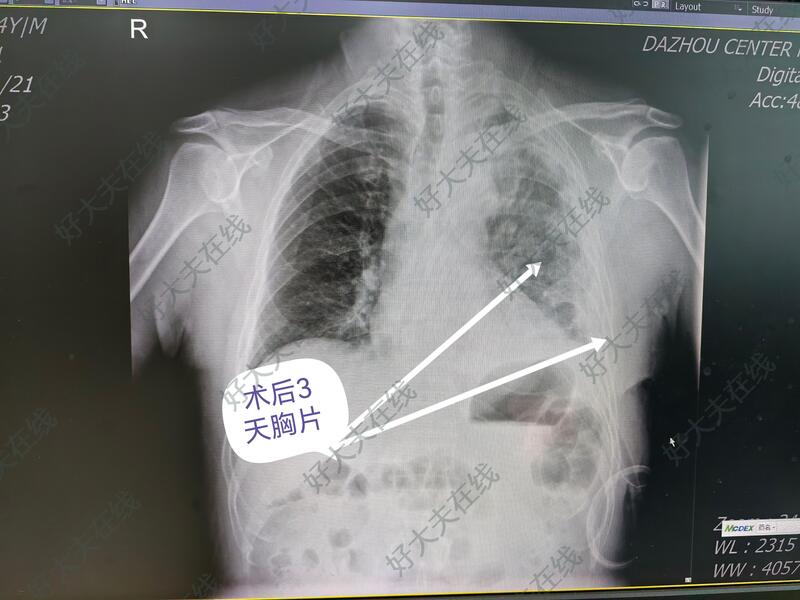

所传照片系第二例病人拔管时的胸片。